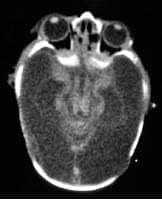

La TAC cerebral (Fotos 3, 4 y 5), muestra alteración difusa en la densidad de la corteza y la sustancia blanca en relación con degeneración quística vista en pacientes con hidranencefalia severa, se conserva la densidad de los territorios de la circulación posterior; se toma resonancia magnética cerebral (Foto 9), siendo los hallazgos compatibles con hidranencefalia, sin signos de hipertensión endocraneana. Por el estado clínico del paciente se considera continuar seguimiento ambulatorio por neuropediatría, neonatología y pediatría.